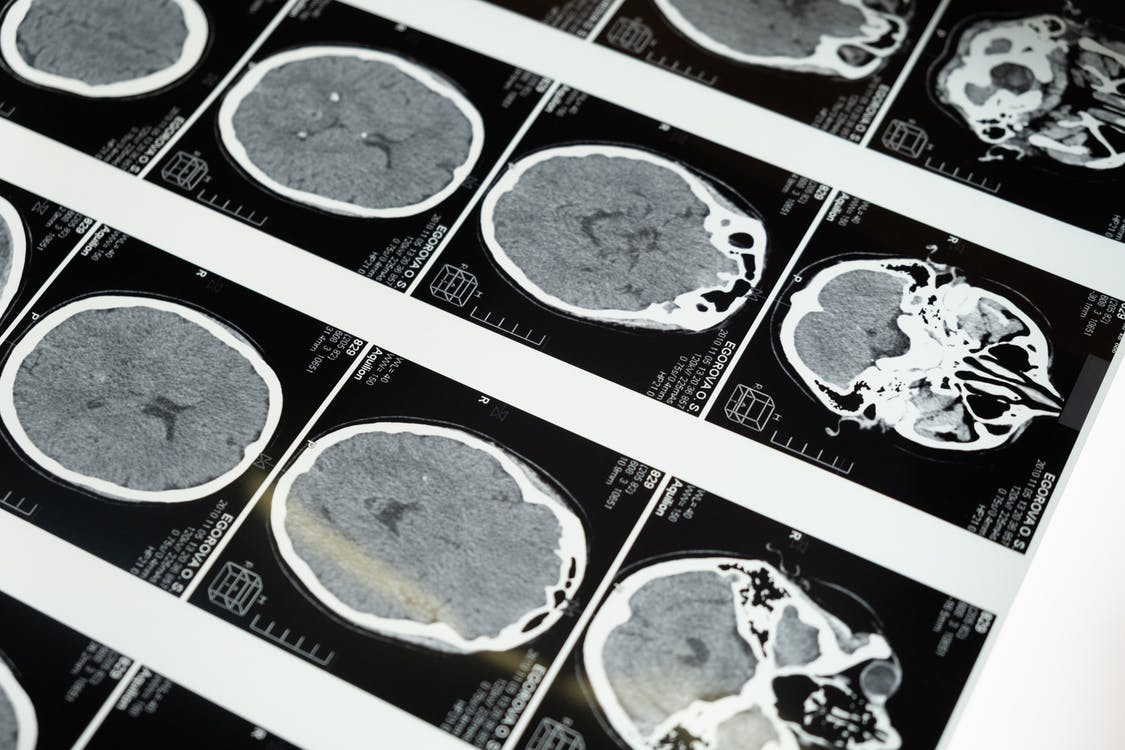

Sabharwal gathered 47 participants from the Suffolk County Mental Health Project, 19 with schizophrenia spectrum disorders and 28 with other psychotic disorders. Additionally, 29 never-psychotic (NP) participants were recruited. Each participant underwent an fMRI scan in order to observe functional connectivity of the amygdala with other brain regions. Global functioning and social functioning were assessed using the Social and Occupational Functioning Assessment scale, and the Quality of Life scale, respectively. Participants performed an emotional face perception task showing emotion and neutral conditions. In each condition, participants were presented with a target face and two probe faces. In the emotion condition, participants had to match a probe face to the emotional expression (fear or anger) of the target face. In the neutral condition, participants had to match the identity of the target face.